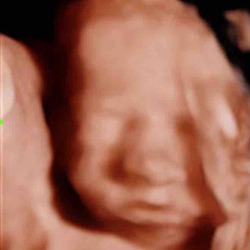

Ik ben vandaag precies 36 weken zwanger en vandaag ook begonnen met het eten van Medjoul dadels. Ik wil er 6 per dag eten.